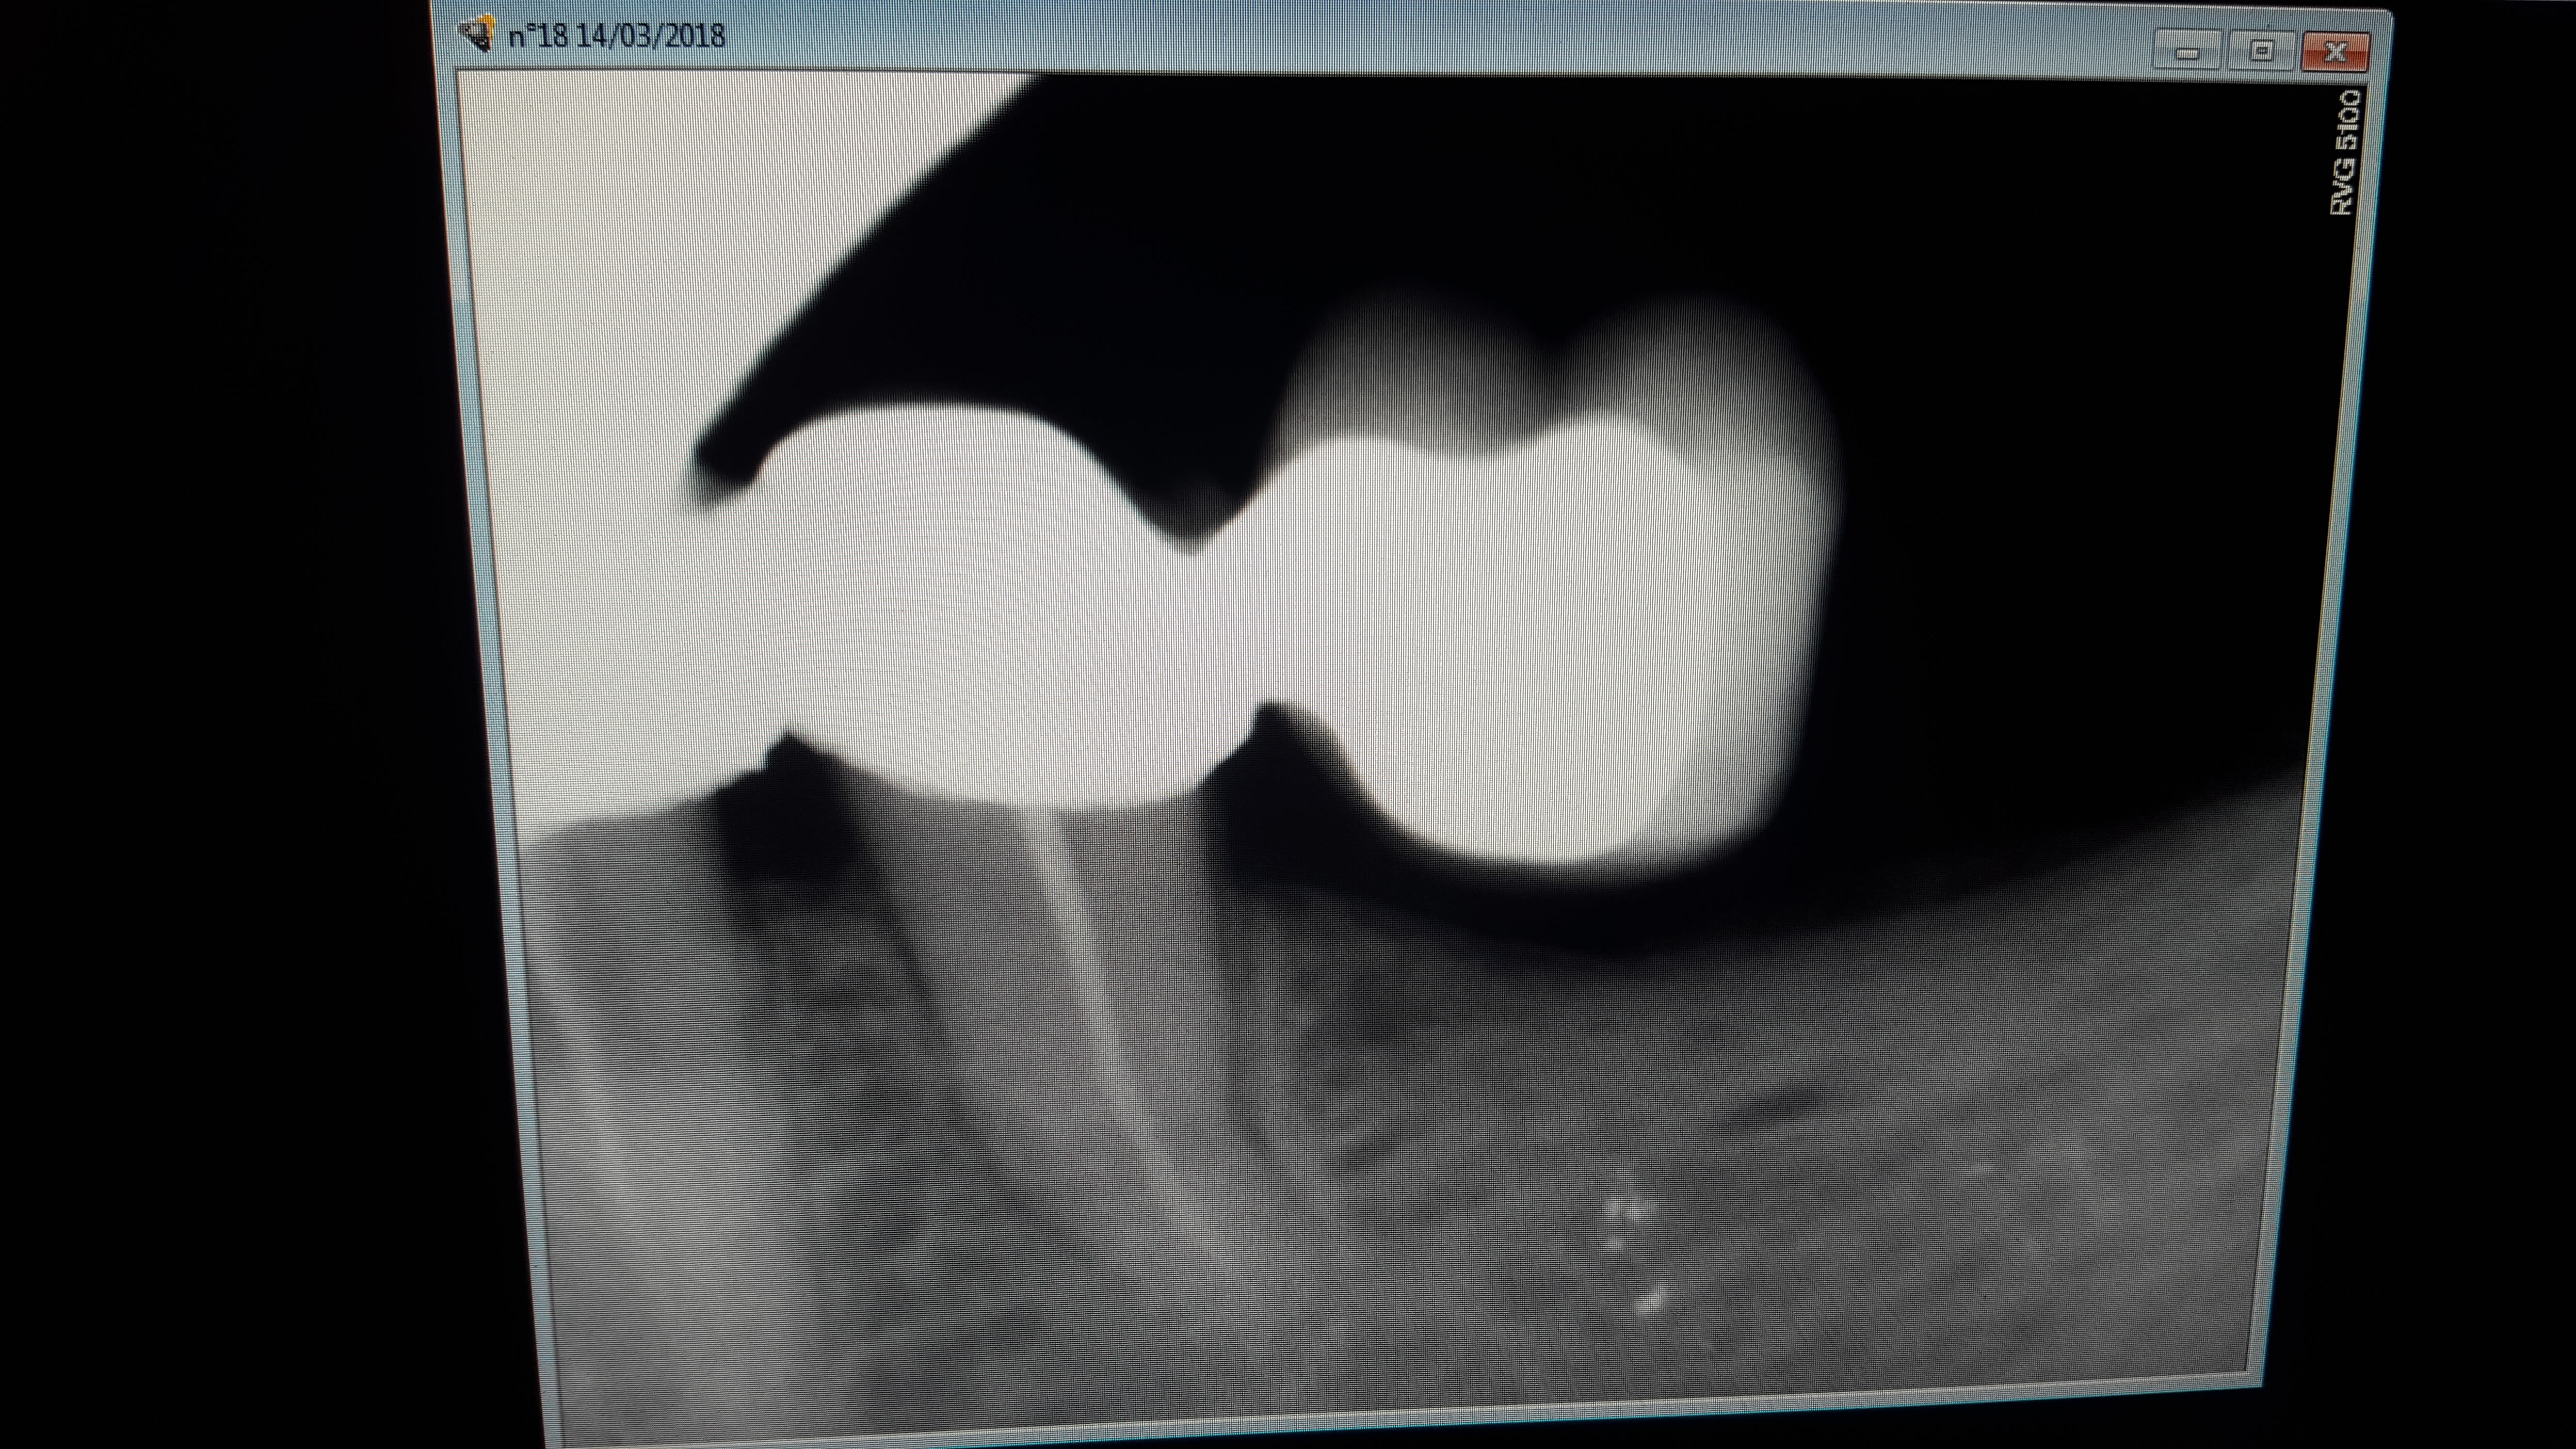

14/03/2018 à 18h14

Je ne m'en lasserai jamais.

Quel sens artistique!